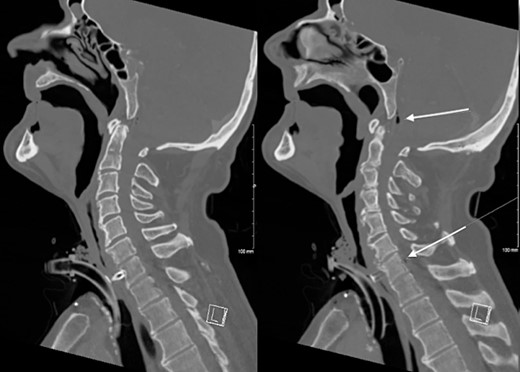

The patient’s C-reactive protein was 304 mg/dL (normal range, <5 mg/dL) and white cell count was 17 × 109/L (normal range, 4.5–11 × 109/L). Chest X-ray and urine dipstick detected no abnormalities. A contrast-enhanced computed tomography (CT) of the neck was performed demonstrating the erosion of the TEP through the posterior wall of the pharynx into the C7 vertebral body with osteomyelitis, an anterior epidural collection, and persistent pharyngocutaneous fistula (Fig. 1).

CT Neck demonstrating erosion of TEP into the C7 cervical resulting in osteomyelitis and a gas containing anterior epidural collection.